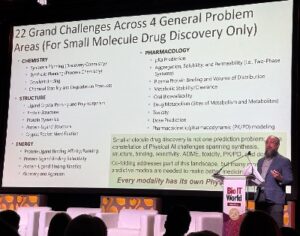

Uncategorized1 week agoBio-IT World Keynote Highlights Collaborative Intelligence in AI-Driven Drug Discovery

BOSTON—A critical part of the conversation around the use of artificial intelligence (AI) in drug discovery focuses on the development of the foundation models that underpin...